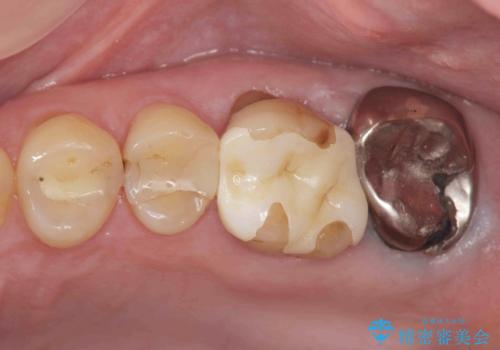

[ 歯肉縁下齲蝕 ] 歯周外科を行った虫歯治療

![[ 歯肉縁下齲蝕 ] 歯周外科を行った虫歯治療の症例 治療前](https://seimitsushinbi.jp/wp/wp-content/uploads/2023/05/a64b0434e936f69092c4868d7fec9b97-500x350.jpg?v=1684994566)